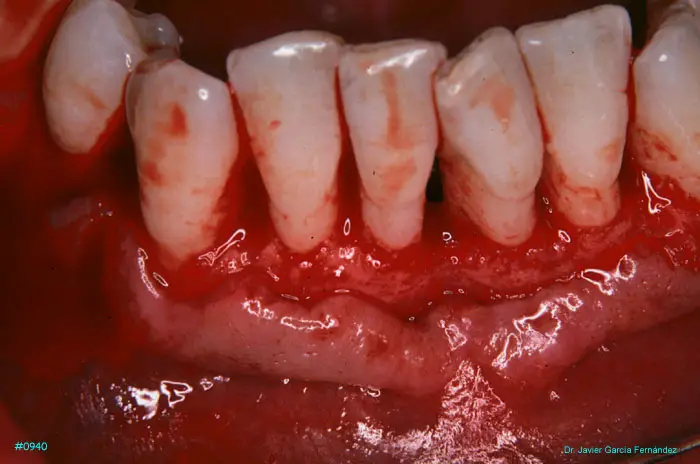

Atlas of Surgical Techniques in Periodontics. Chapter III. Atlas de Técnicas Quirúrgicas en Periodoncia